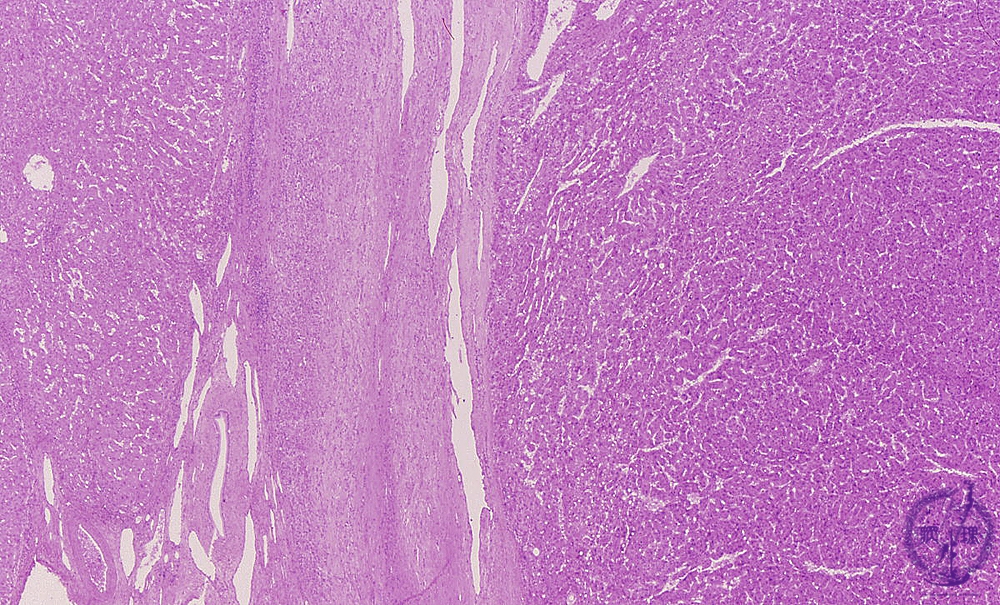

• 10.Liver

• š(12)Hepatocellular carcinoma

Microscopic finding (HE stain, low power view): On the right side is solid type hepatocellular carcinoma. On the left side is the background cirrhotic liver. The two areas are separated by fibrous capsule.

Click the image to see the enlarged image.

• There is no guidance by arrows.